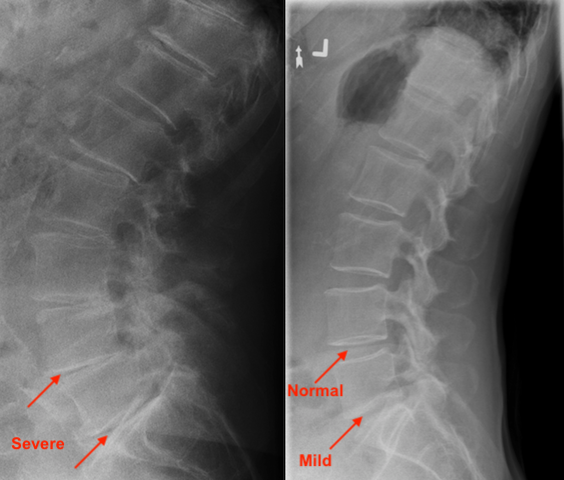

Osteoarthritis (OA) is a condition where the joints in the spine and extremities become inflamed and wear out gradually. Disc degeneration can also be associated with OA. This is a condition where the shock absorbing cushions between the bones in the spine wear out. OA and disc degeneration are the spinal “cavities” of the spine.

Because there are so many risk factors, there’s no hard evidence that chiropractic care ALONE will help prevent osteoarthritis and disc degeneration. However, because chiropractic care helps improve mobility and alignment of the spine, seeing a chiropractor regularly would at least help slow down the progression of osteoarthritis and disc degeneration. Chiropractic care also helps to manage the pain associated with osteoarthritis and disc degeneration.